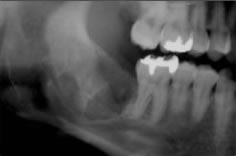

• 初診時

右下の親知らずと手前の歯が下あごに埋まっています。

• 抜歯2週間後の状態

抜歯した部分は、徐々に骨が出来上がってきます。

抜歯後、半年程で骨は出来上がります。

健康保険適用のため治療費は約4,000円(3割負担)。

治療期間は、抜歯後1週間ほどで抜糸を行い問題なければ終了。

治療のリスクは、術後の疼痛(ドライソケット)・術後の感染・下歯槽神経麻痺・上顎洞との交通などがあります。